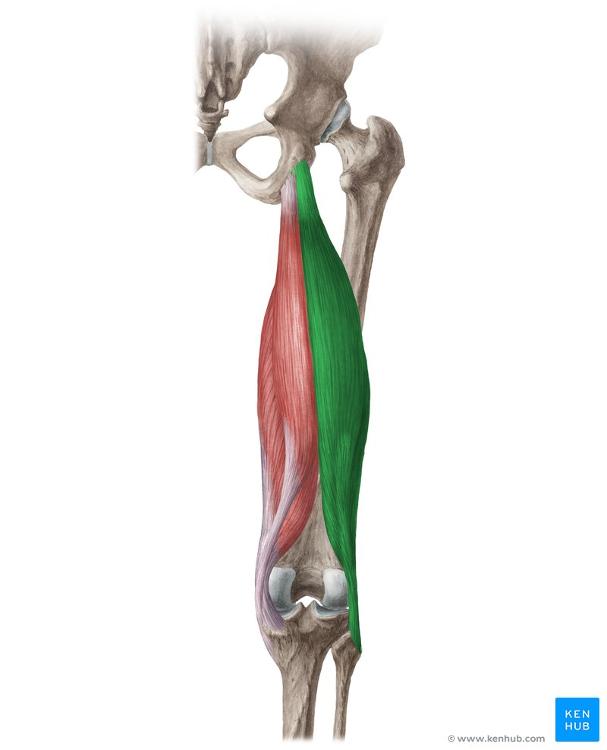

biceps femoris

O: long head- ischial tuberosity

short head- linea aspera

I: head of fibula

A: flexes knee and

long head- extends thigh

N: long head- tibial nerve

short head- common peroneal nerve